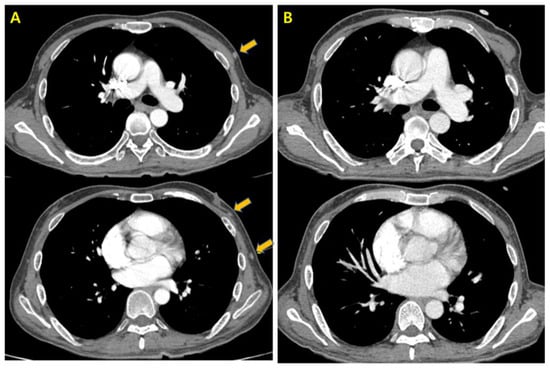

2. Case Presentation